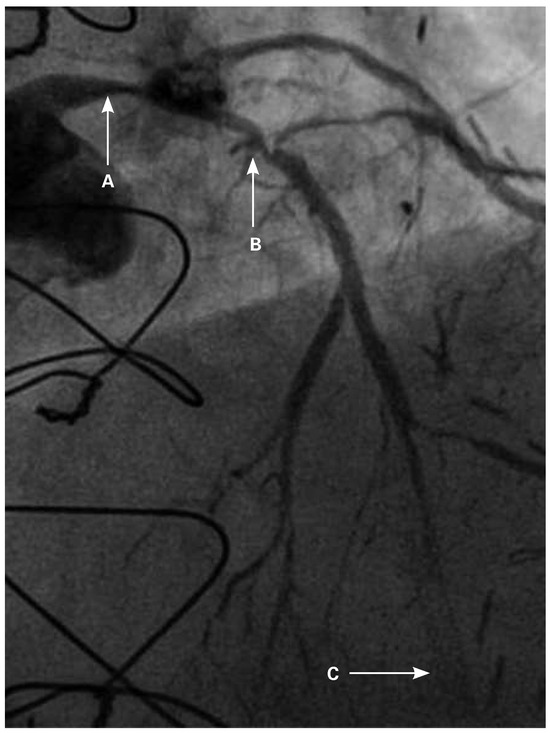

Coronary angiography of the left coronary system demonstrated severe left main stem (LMS) disease (Figure 1). The severe LAD in-stent restenosis was very eccentric and appeared to be restricting the origin of a sizeable diagonal branch, which also had severe disease. Distally, the LAD was occluded at the point where another stent had been inserted previously and just beyond a large septal perforator. The Cx had severe ostial disease and gave rise to a heavily diseased first obtuse marginal branch. The remainder of Cx and right coronary artery (RCA) systems were occluded proximally, with absent collaterals. The only patent graft was the LIMA, anastomosed very distally to the LAD (Figure 2). Following discussion, it was felt that neither Cx nor RCA were suitable targets for surgery and we therefore undertook intervention to the LMS and LAD / first diagonal bifurcation.

Figure 2. Straight PA view of the LIMA anastomosis to distal LAD.